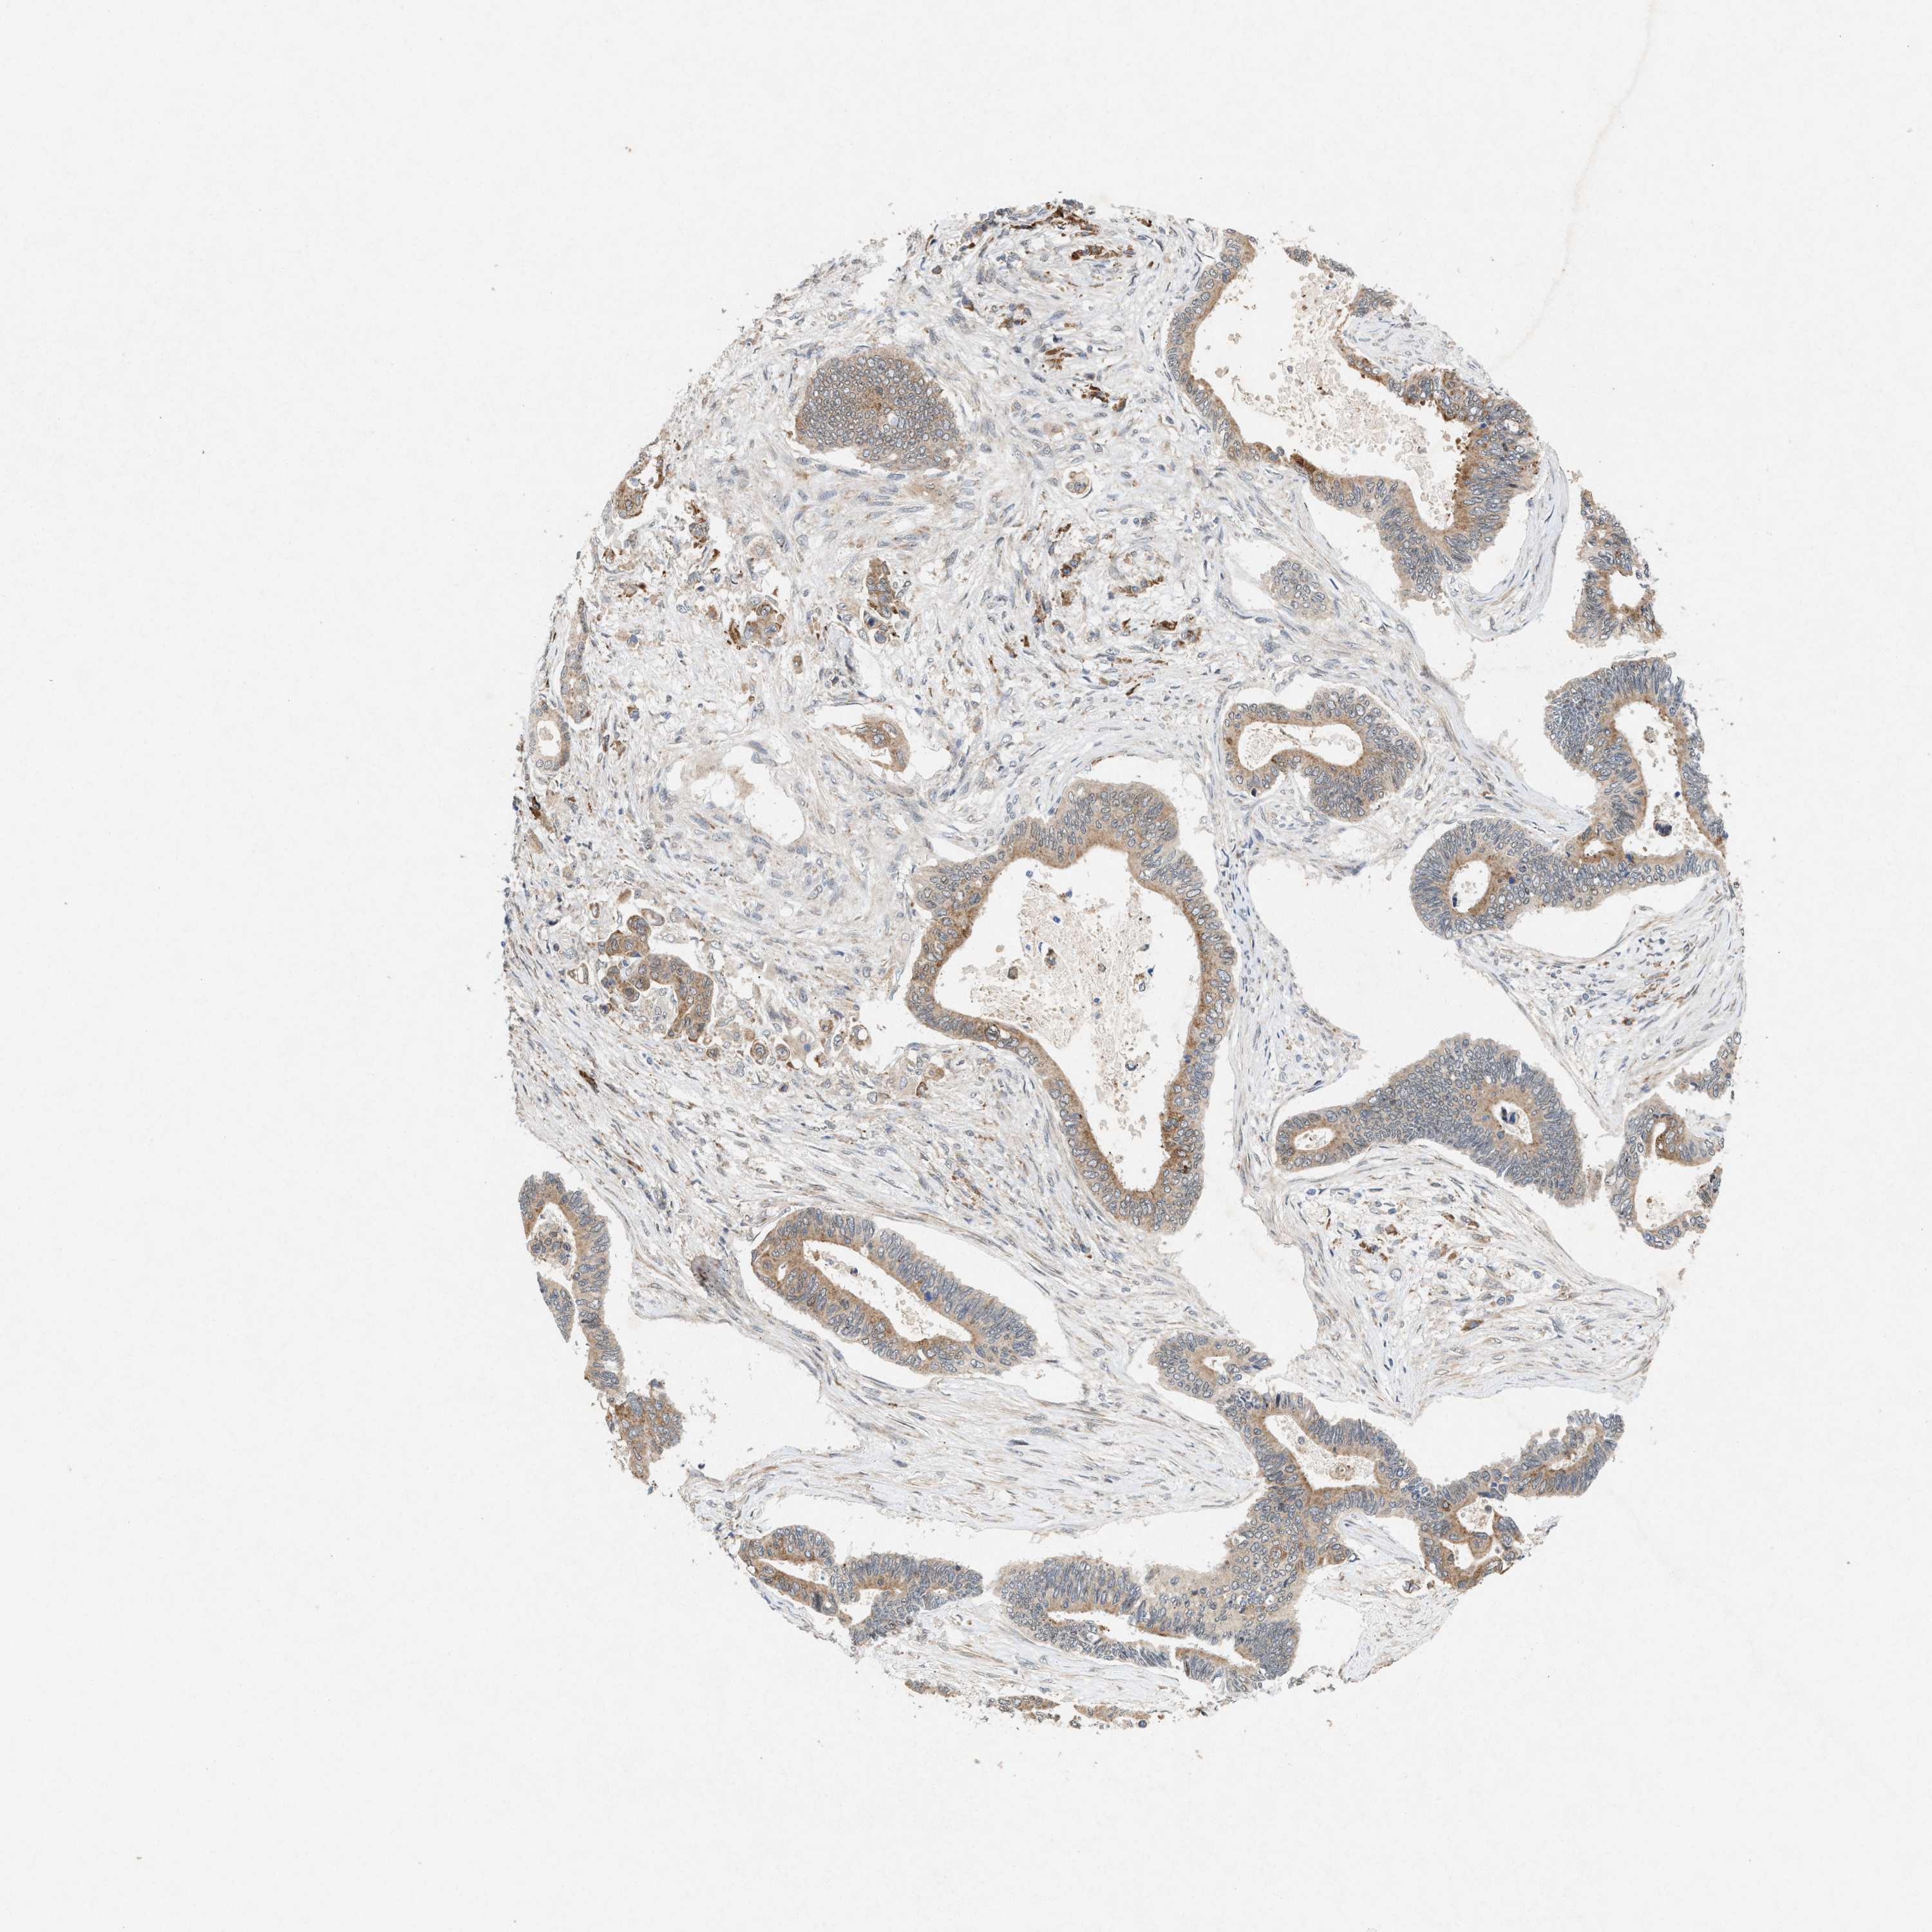

PANCREATIC CANCER - Protein expressioni

A mouse-over function shows sample information and annotation data. Click on an image to view it in a full screen mode. Samples can be filtered based on level of antibody staining by selecting one or several of the following categories: high, medium, low and not detected. The assay and annotation is described here.

Note that samples used for immunohistochemistry by the Human Protein Atlas do not correspond to samples in the TCGA dataset.

Antibody stainingi

Antibody staining in the annotated cell types in the current human tissue is reported as not detected, low, medium, or high, based on conventional immunohistochemistry profiling in selected tissues. This score is based on the combination of the staining intensity and fraction of stained cells.

Each image is clickable and will lead to virtual microscopy that enables deeper exploration of all samples and also displays staining intensity scores, fraction scores and subcellular localization as well as patient and tissue information for each sample.

Antibody HPA022274

Staining

High

Medium

Low

Not detected

Intensity

Strong

Moderate

Weak

Negative

Quantity

>75%

75%-25%

<25%

None

Location

Nuclear

Cytoplasmic/membranous

Cytoplasmic/membranous,nuclear

Adenocarcinoma, NOS